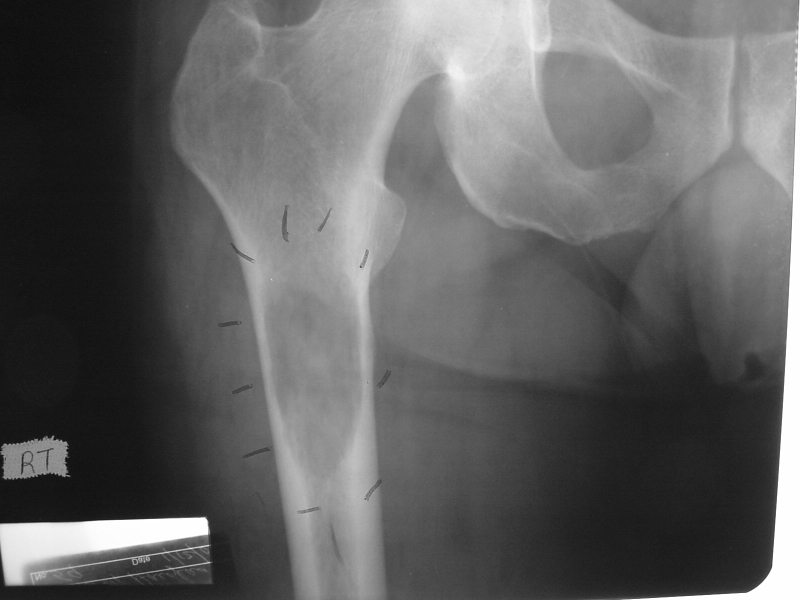

16yo female with painful thigh. Top Diagnosis? How will she present to you? Radiographic findings typical of this?

Ewing Sarcoma

12 yo male comes in with fever, and painful left hip. Below is his XR. Diagnosis? Managment? Treatment?